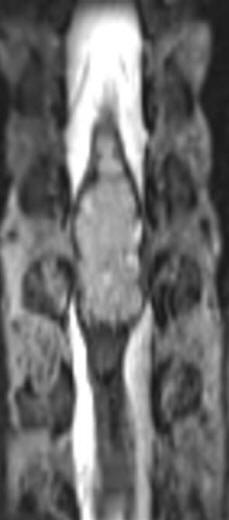

MRI in coronal and sagittal sections showing the tumor before surgery

Intraoperative MRI Sagittal showing radical removal of the tumor.

Intraoperative MRI axial views showing that the spinal cord mass was mainly in the left side supporting the fibertraking data.